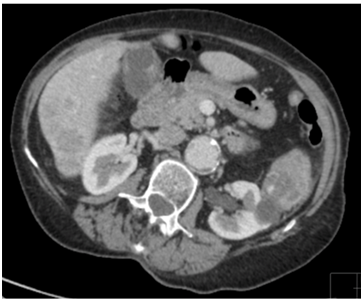

Our patient was a 79-year old female with severe progressive chronic obstructive pulmonary disease (COPD) on home oxygen, type 2 diabetes, hypertension and angina. She presented with type 1 respiratory failure and chest pain in December 2015. A computed tomography pulmonary angiogram (CTPA)4 months prior to this admission, showed no pulmonary embolism but did show a solitary liver lesion (Figure 1), measuring 2.5cm x 2.8cm that was suspicious for metastasis. A subsequent contrast-enhanced staging CT abdomen and pelvis demonstrated multiple liver metastases (Figure 2) with a 5.5cm solid-cystic lesion arising from her left kidney. After discussion with the Hepatobiliary multidisciplinary team (MDT), she underwent a percutaneous biopsy of the liver lesions, which showed metastatic carcinoma of indeterminate primary. She was seen by our Oncologists and was deemed suitable only for palliative treatment at this stage due to a presumed metastatic renal cancer and her multiple co-morbidities.

Figure 1: CTPA showing solitary liver lesion in August 2015.